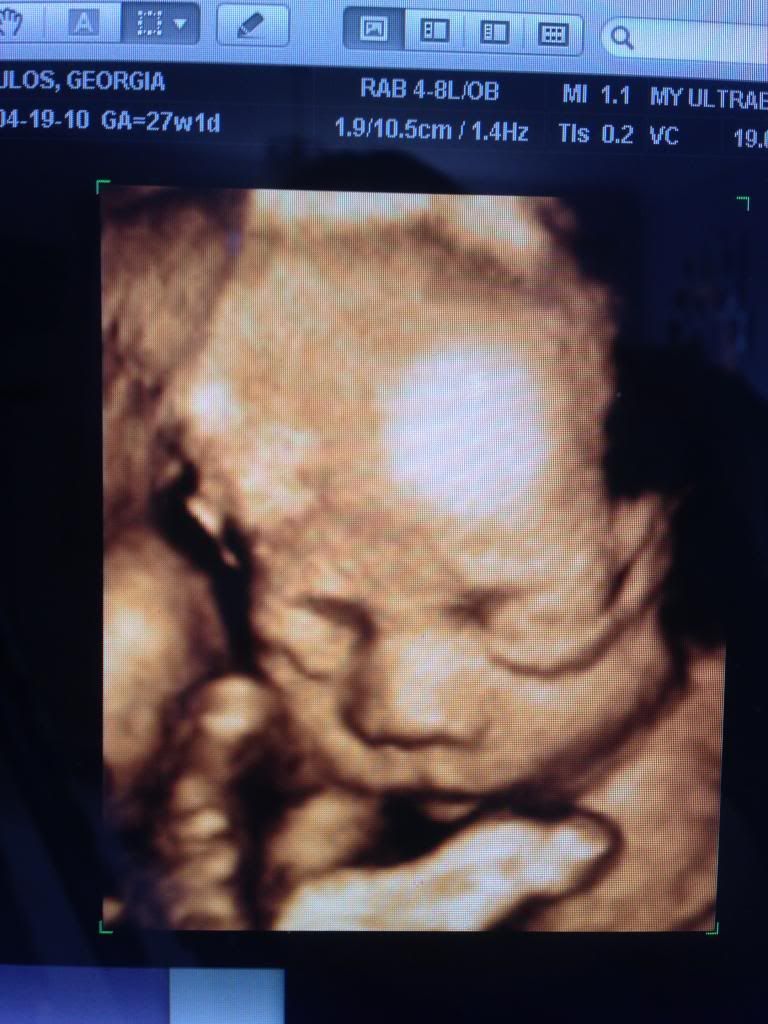

The “best” time to come in for a 3d/4d ultrasound really depends on what you want to see. Often, doctors order a 3d ultrasound to take a closer look at why a pregnancy may not be progressing as. If your doctor agrees to offer a 3d or 4d ultrasound as a professional courtesy to you, the ideal time to get them done is toward the. Below is a breakdown on what to expect during an ultrasound depending on how. Fetal anatomical ultrasound is essential to detect any anomalies in a baby.

When is the Best Time to Get a 3D Ultrasound? Mother Nurture Ultrasound